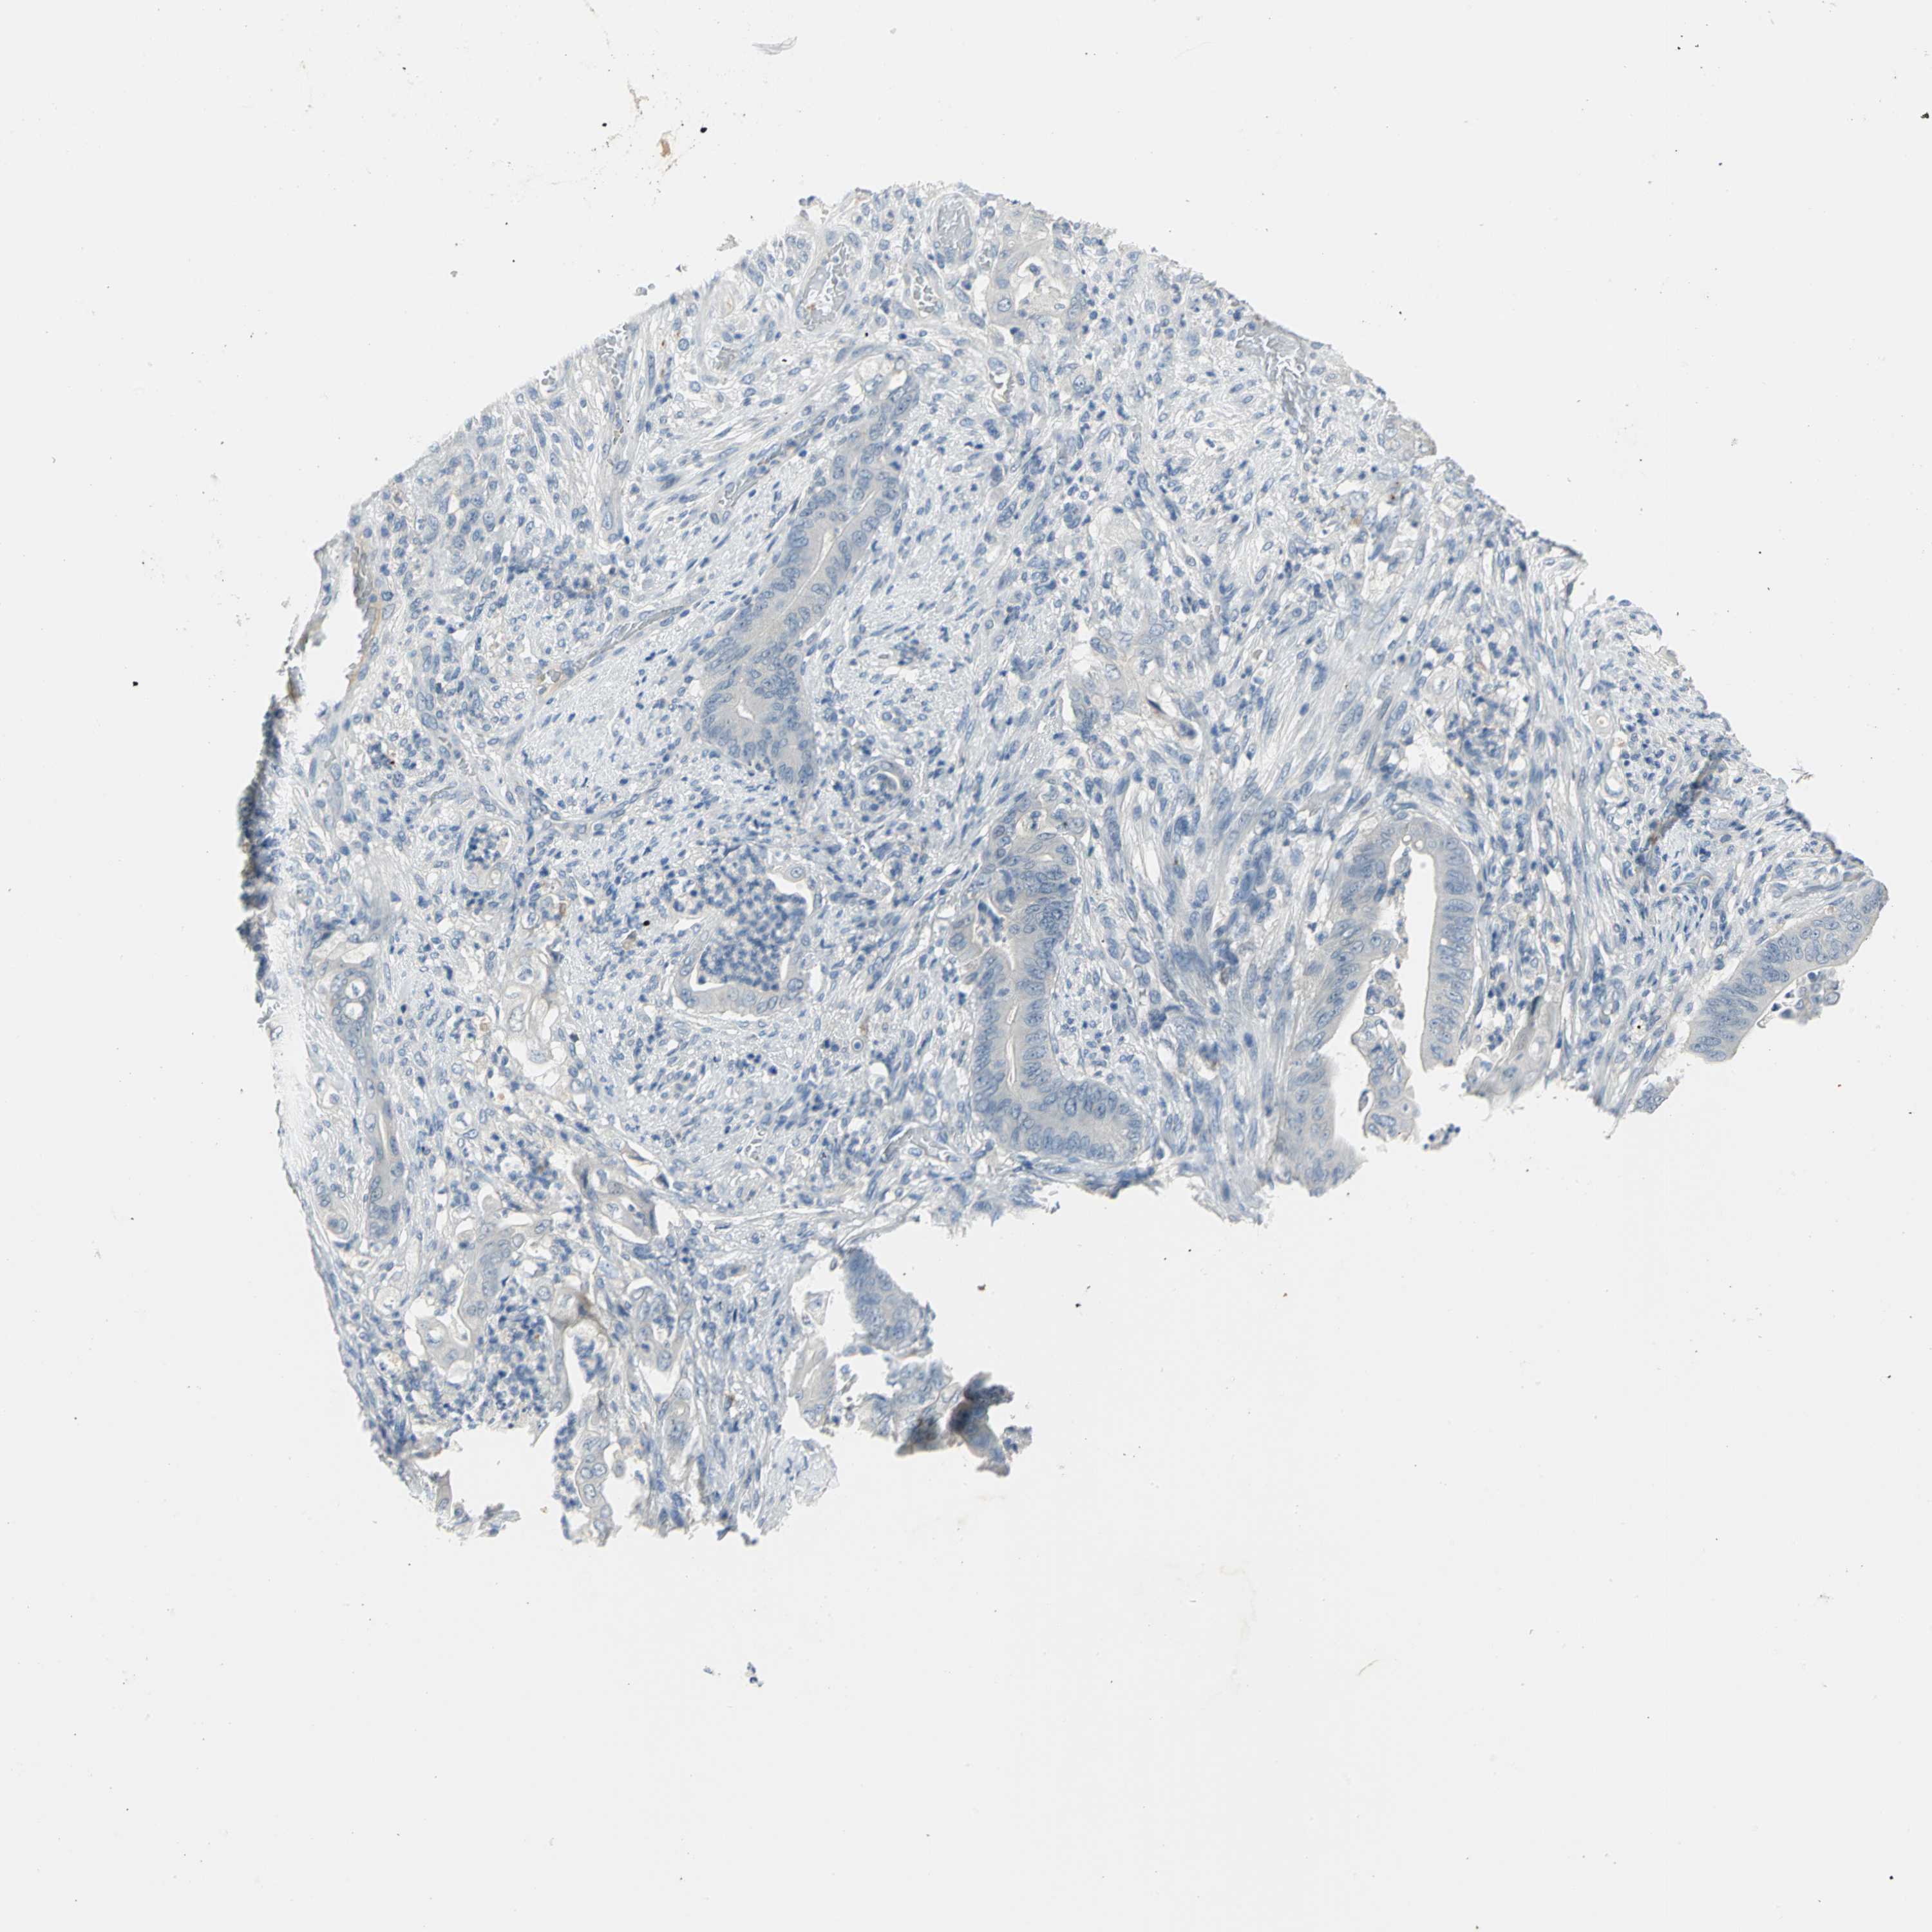

STOMACH CANCER - Protein expressioni

A mouse-over function shows sample information and annotation data. Click on an image to view it in a full screen mode. Samples can be filtered based on level of antibody staining by selecting one or several of the following categories: high, medium, low and not detected. The assay and annotation is described here.

Note that samples used for immunohistochemistry by the Human Protein Atlas do not correspond to samples in the TCGA dataset.

Antibody stainingi

Antibody staining in the annotated cell types in the current human tissue is reported as not detected, low, medium, or high, based on conventional immunohistochemistry profiling in selected tissues. This score is based on the combination of the staining intensity and fraction of stained cells.

Each image is clickable and will lead to virtual microscopy that enables deeper exploration of all samples and also displays staining intensity scores, fraction scores and subcellular localization as well as patient and tissue information for each sample.

Antibody HPA004098

Staining

High

Medium

Low

Not detected

Intensity

Strong

Moderate

Weak

Negative

Quantity

>75%

75%-25%

<25%

None

Location

Nuclear

Cytoplasmic/membranous

Cytoplasmic/membranous,nuclear

Adenocarcinoma, NOS

Adenocarcinoma, High grade